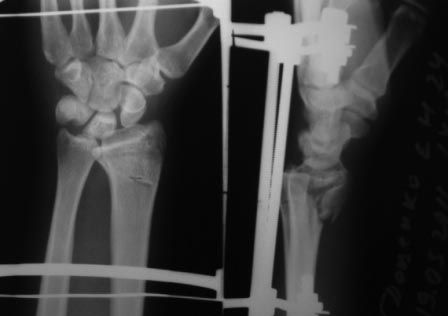

Re: перелом луча

Извините за позднее вмешательство в Вашу полемику. Хотелось начать по порядку. На мой субъективный взгляд одномоментного сочетание методов накостного и чрескостного остеосинтеза уменьшают достоинства обоих. Достоинства накостного остеосинтеза: более ранняя социальная реабилитация больного, т.к. не требуется специального ухода (как при использовании ЧКДО). Достоинство аппарата внешней дистракции - меньшая травматичность по сравнению с накостным остеосинтезом.

Что касается вариантов накостного остеосинтеза: возможно два варианта - остеосинтез волярной пластиной или фрагмент-специфическая фиксация отломков по Мedoff, но в связи с тем что перелом внутрисуставной очень часто требуется артротомия, т.к. наличие даже ЭОПа не обеспечивает точного восстановления суставной поверхности лучевой кости. Второй менее травматичный способ визуализации репозиции внутрисуставных отломков, признаный рутинным в ходе заседания EWAS в рамках FESSH 2010 (конгресс европейского общества хирургов кисти), проходивший в Бухаресте, это артроскопия кистевого сустава. Думаю данный способ вряд ли доступен в данном случае.

Остается как самый уместный способ - чрескостный остеосинтез с применением аппарата внешней фиксации: т.к. он весьма бюджетный и позволяет достичь необходимой репозиции.